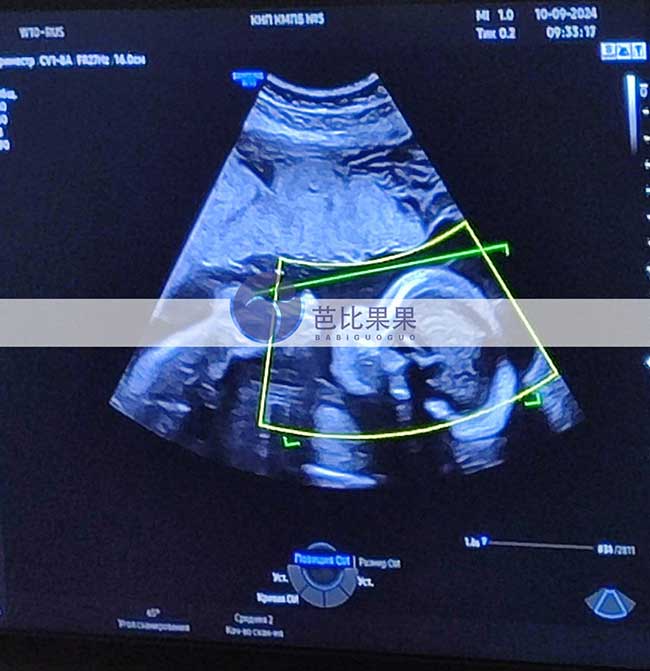

L先生在格鲁吉亚医院移植胚胎匹配的试管妈妈做四维彩超

L先生在格鲁吉亚医院移植胚胎匹配的乌克兰试管妈妈做四维彩超,检查确认是个活泼可爱的男宝宝,身体发育很健康~